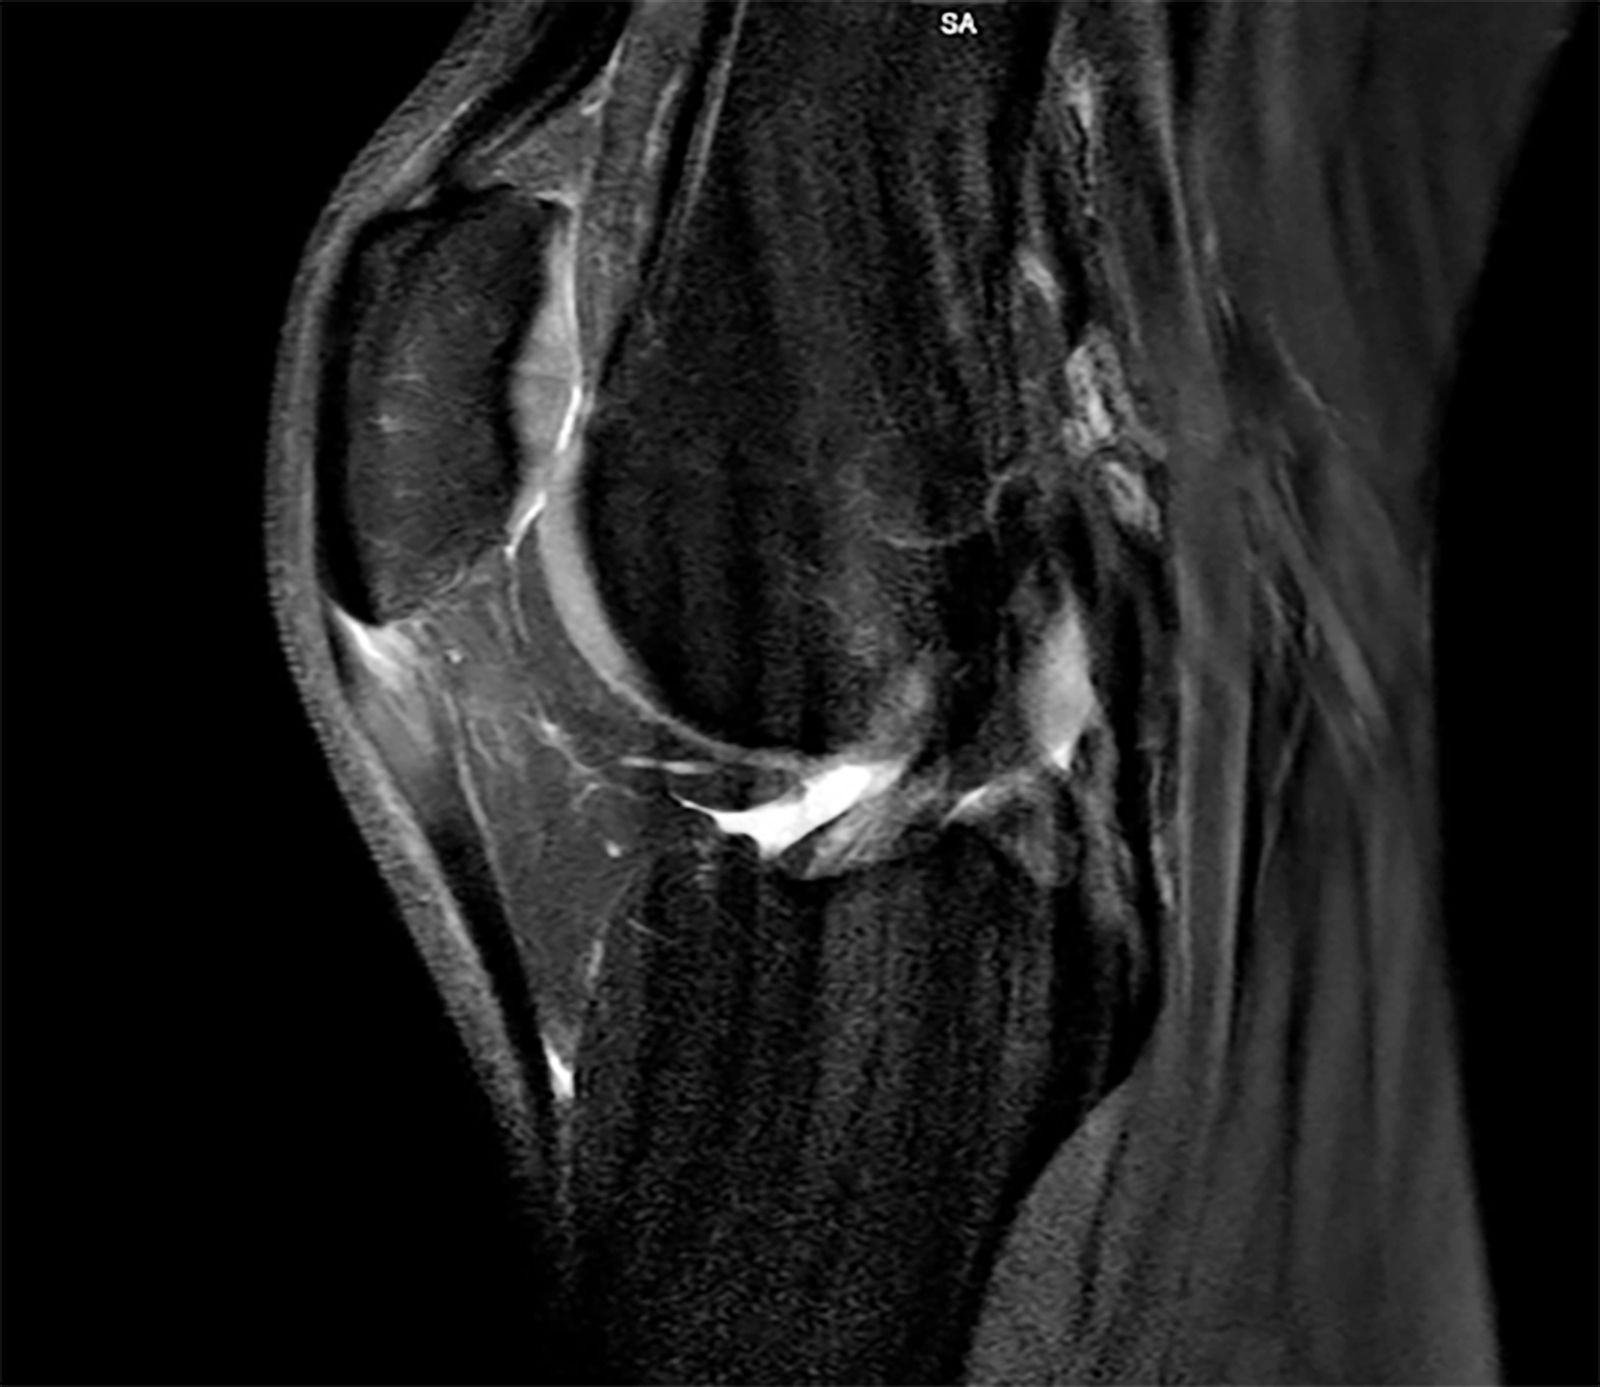

Im Mittelpunkt steht bei der Tendinopathie ein ungünstiges Verhältnis zwischen chronischer Belastung und Belastbarkeit der Sehne durch vermehrte Bildung von Typ-III-Kollagen. Prinzipiell wird Typ-III-Kollagen zwar in frühen Heilungsphasen vermehrt gebildet, aber später auch wieder durch den stabileren Kollagentyp I ersetzt. Kurzfristig ist eine gewisse Zunahme von Typ III daher Teil des natürlichen Reparationsprozesses. Bleibt jedoch ein hoher Typ-III-Anteil im Sehnengewebe bestehen, führt das zu einer qualitativ minderwertigen Gewebestruktur, da Typ III mechanisch weniger belastbar ist als Typ I – das ist das narbig veränderte Sehnenareal, das im Ultraschall als hypoechogene Zone erscheint (Abb. 1). Im weiteren Verlauf erfolgt das remodeling der Sehne um dieses tendinopathische Areal herum und es kommt zur Größenzunahme des Gewebes [2, 4, 9]. Um diesen chronischen Prozess der Tendinopathie zu durchbrechen und eine strukturelle Heilung zu ermöglichen, kann das erwähnte Verfahren als eine Form der perkutanen ultraschallgestützten Tenotomie angewendet werden. Das Unternehmen TENEX (Tenex Health Inc.) hat ein eigenes Gerät entwickelt, das krankhaftes Sehnengewebe durch eine Ultraschallsonde mit Saug- und Spülsystem entfernen kann. Dabei kommt ein handgeführtes Instrument mit einer doppellumigen Ultraschall-Vibrationsnadel zum Einsatz, das über eine Stichinzision unter sonografischer Sicht in das tendinopathische Areal eingebracht werden kann (Abb. 2). Der postulierte Wirkmechanismus basiert auf der Phakoemulsifikation (Zertrümmerung) von nekrotischem Sehnen- und Narbengewebe, wobei gesundes Gewebe aufgrund anderer biomechanischer Eigenschaften intakt bleibt – analog zur Behandlung des Grauen Star am Auge. In Folge kommt es zu einer gezielten Auslösung einer Entzündungsreaktion, um Reparaturprozesse anzukurbeln, sodass die Sehne wieder im gesunden heilen kann. Man drückt quasi den reset button der Sehnenheilung [3, 6, 8].

Das ganze System ist dann 2018 zusammengebrochen, nachdem diese Reizung / Symptomatik an der Spitze so sehr zugenommen hatte, dass klar war, dass das behandlungsbedürftig war. Wir hatten damals im 11/ 2018 ein MRT gemacht und festgestellt, dass die Entzündung an der Patellaspitze so groß wie noch nie war. Daraufhin gab es eine einige Wochen Pause und ACP Therapie. Nach der Therapie habe ich fast das restliche Jahr mich einem Return-To-Sports-Programm gewidmet, um Schritt für Schritt wieder an die Belastung herangeführt zu werden. Das hatte leider nicht den erhofften langfristigen Erfolg gebracht, sondern es ist in den Folgejahren immer wieder unterschiedlich stark aufgeflammt und hat mich in meiner Sportlichkeit als Hochspringer gebremst.

Ende 2023 war ich zuversichtlich das Problem durch gezieltes Training der Sehne kontrollieren zu können. Ich besuchte die Charité in Berlin, um dort einen exakt für meine Sehne angepassten Trainingsplan nach der Berliner Methode zu ermitteln und umzusetzen. Leider musste ich in der folgenden Hallensaison 2024 feststellen, dass das nicht ausreichend war und die Sehne doch medizinische Aufmerksamkeit braucht. Das Sehnentraining war zu diesem Zeitpunkt bereits zermürbend und schwer aufrecht zu erhalten. Ein Angebot der Praxis im September 2022, noch einmal den Zustand zu überprüfen und gegebenenfalls mit fokussierter Stoßwelle oder ACP in der Off-Season zu arbeiten, hatte ich nicht wahrgenommen, da ich fester Überzeugung war, an dem Punkt das Problem durch korrektes Training und Pflege der Sehne weiter im Griff haben zu können oder abzuschließen. Die Saison 2023 war eben weitestgehend beschwerdefrei! Nachdem ich mir einen Längsriss in einem Wettkampfsprung im Februar 2024 an der Sehne hinzugezogen hatte, war ich wieder in medizinischer Betreuung und wir haben die Sehne erneut unter die Lupe genommen haben. Dabei mussten wir feststellen, dass die Tendinopathie nach wie vor vorhanden war und zugenommen hatte. Das war bitter zu dem Zeitpunkt, da ich mich schon in der unmittelbaren Vorbereitung vor den Olympischen Spielen 2024 befand. Der Längsriss konnte sehr erfolgreich mit ACP therapiert werden und war dann auch in kürzester Zeit ausgeheilt. Allerdings, kurz vor Saisonbeginn 2024, hatte sich die Symptomatik an der Spitze erneut so sehr zugespitzt, dass es mir nicht mehr möglich war, normal zu rennen, geschweige denn zu springen.

Als ich Ende April mit extremen Beschwerden an der Patellaspitze aus einem Trainingslager zurückkam und direkt montags zur Untersuchung in die Praxis nach dem MRT kam, wurde ich über die TENEX-OP-Methode informiert, welche auch als vorletzte Eskalationsstufe zur Behandlung von Tendopathien gilt. Das war dann die Last-Minute-Chance, 100 Tage vor Paris, um die Möglichkeit zu kriegen, an den Olympischen Spielen teilzunehmen, dachte ich mir. Qualifiziert war ich schon, vor allem durch meine sehr starke Vorjahresleistung und bis zur Verletzung erfolgreiche Hallensaison. Grundsätzlich war ich auch in einem sehr guten Trainingszustand – eben bis auf die Patellasehne. Nach kurzer Bedenkzeit habe ich innerhalb von einer Woche mich für den minimal invasiven Eingriff entschieden. In der ersten Maiwoche sollte die OP durchführt werden, um noch so viel Zeit wie möglich vor den Olympischen Sommerspielen Anfang August zur Regeneration zu haben. Ich kann mich noch gut erinnern, als alle Orthopäden der Praxis versammelt in einem Raum waren und mit mir und meinem Trainer gemeinsam diese Option diskutiert haben. Ich hatte keine Zweifel und war fest überzeugt, dass das jetzt der Weg ist, den ich einschlagen muss, um eine Chance zu bekommen! Ich war dankbar für die weiteren Optionen und neuen möglichen Lösungen, die mir hier aufgezeigt wurden. Vor allem bei so einer langjährigen Symptomatik habe ich schon von vielen Ansätzen gehört und viele auch ausprobiert. Ich weiß, dass es immer ein Risiko gibt und man in jede Therapie Zeit und Geduld investieren muss, um festzustellen, ob es für einen funktioniert oder nicht. Aber in diesem Fall gab es nicht mehr viel Zeit für Experimente.

In der Zwischenzeit konnte ich nach längerer Pause wieder umfangreicher trainieren. Die Patellasehne ist auch bei der letzten Bildgebung aus dem Januar deutlich besser als die letzte vor der OP, so das man nur von einer leichten Reizung sprechen kann. Sie war die meiste Zeit symptomfrei, allerdings ist das Problem nach wie vor noch nicht ganz aus der Welt. Sehnentraining und Pflege gehören weiterhin zu meinem Trainingsalltag. Mittlerweile auch für mehrere Sehnen an meinem Sprungbein, Plantar/ Achilles/ Patella. Sicherlich ist das langsam altersbedingt in meiner Sportart, was aber erst einmal nichts über die Leistungsfähigkeit aussagt, sondern nur weitere Anpassung des Trainings erfordert! Ich habe in der gesamten Zeit der Tendopathie beinahe jede Therapieform merhfach genutzt, Hyaluron, Traumeel, ACP, Milchsaure, Aktovegin, Blutegel, Röntgenreiz (3x!), Infrarot, f-ESWT, EPTe (Elektrolyse) und sicher habe ich sogar noch etwas vergessen. Ich würde die Entscheidung für die OP noch einmal treffen, allerdings mit ausreichend Zeit und Nachbereitung. Vielleicht kann man das TENEX sogar früher in Erwägung ziehen.